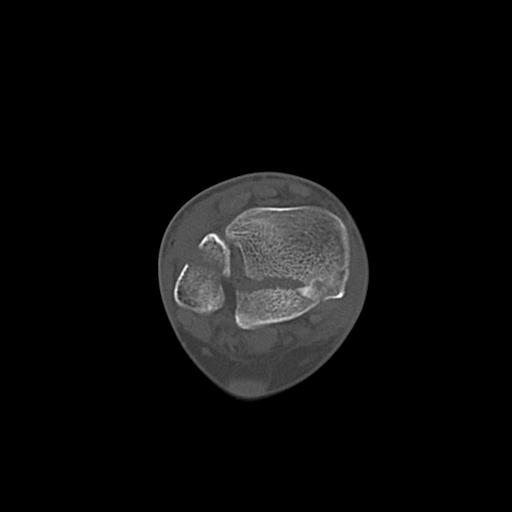

102755 1/4 2R 1/15 2R 右足関節 68歳女性 右三果脱臼骨折